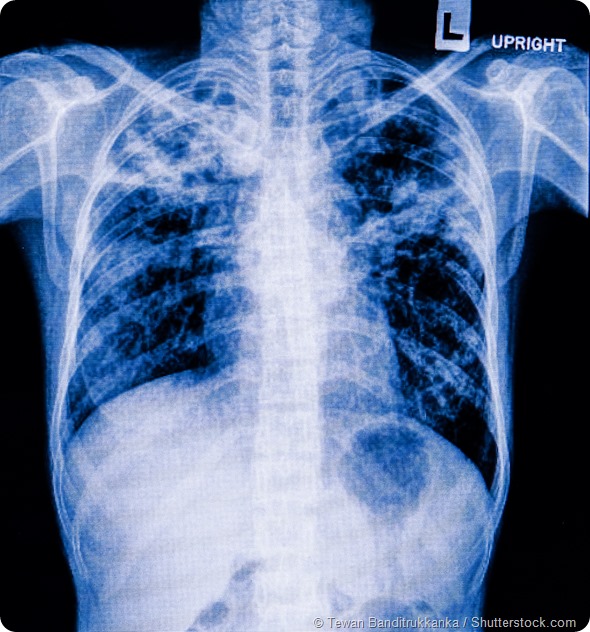

%26Lung_with_Influenza_(right)from_a_case_of_influenza_showing_microscopic_disease_pathology_of_flu-vetpathologist-1000.jpg)

Normal Lung (left) and Lung with Influenza (right). Comparative twin images of normal healthy lung in contrast to lung from a case of influenza showing microscopic disease pathology of flu. © vetpathologist / Shutterstock.com.